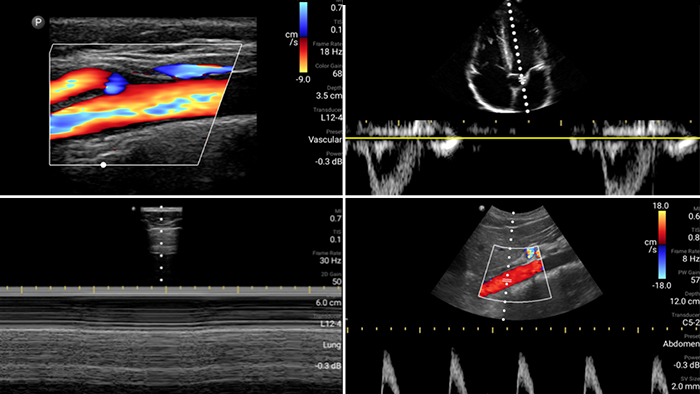

Evalúe, diagnostique y trate a sus pacientes en minutos con un examen POCUS de puntos múltiples.

Lumify puede ayudar a evaluar a los pacientes más rápido y a mejorar la precisión en el diagnóstico de las causas comunes de disnea y otras afecciones pulmonares.

• Rango extendido de frecuencias de operación de 4 a 1 MHz • 2D, Doppler a color, Modalidad M, XRES avanzado e imágenes armónicas multivariables • Imágenes de alta resolución para aplicaciones abdominales y cardíacas: las optimizaciones de preajustes de imágenes cardíacas, gineco-obstétricas, pulmonares, abdominales y FAST de Lumify ayudan a la tecnología que salva vidas en entornos prehospitalarios